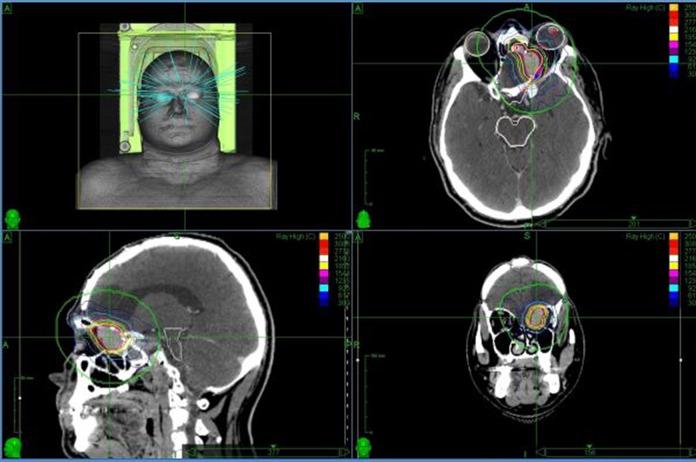

Data on patients treated for intraorbital lesions from solid malignancies were retrospectively collected. All patients underwent treatment with CyberKnife system. We analyzed local control, response rate, symptoms control, progression-free survival and overall survival, acute and late toxicity.

From January 2012 to May 2017, 20 treatments on 19 patients were performed, with dose ranging from 24 to 35 Gy in 1 to 5 fractions, prescribed at an average isodose line of 79.5% (range: 78-81). After a mean follow-up of 14.26 months (range: 0-58), overall response rate was 75%, with 2 and 4 patients presenting a partial and complete response, respectively. Mean time to best measured response was 15.16 months (range: 2-58). Thirteen patients were alive, with a local control rate of 79%. Mean time to local progression was 5 months (range: 3-7). Three patients reported improvement in symptoms after treatment. Mean planning target volume dose coverage was 97.2% (range: 93.5-99.7). Mean maximum dose (D max) to eye globe, optic nerve, optic chiasm, and lens was 2380.8 cGy (range: 290-3921), 1982.82 cGy (range: 777.3-2897.8), 713.14 cGy (range: 219.5-2273), and 867.9 cGy (range: 38-3118.5). Four patients presented acute toxicity.

2012 年 1 月至 2017 年 5 月,19 名患者接受了 20 次治疗,剂量范围为 24-35 Gy,分为 1-5 个分次,处方平均等剂量线为 79.5%(范围:78-81)。中位随访 14.26 个月(范围:0-58)后,总反应率为 75%,2 例和 4 例患者分别出现部分缓解和完全缓解。最佳测量反应的平均时间为 15.16 个月(范围:2-58)。13 名患者存活,局部控制率为 79%。局部进展的平均时间为 5 个月(范围:3-7)。3 名患者治疗后症状改善。平均计划靶区剂量覆盖率为 97.2%(范围:93.5-99.7)。眼球、视神经、视交叉和晶状体的最大剂量(D max)平均值分别为 2380.8 cGy(范围:290-3921)、1982.82 cGy(范围:777.3-2897.8)、713.14 cGy(范围:219.5-2273)和 867.9 cGy(范围:38-3118.5)。4 名患者出现急性毒性。